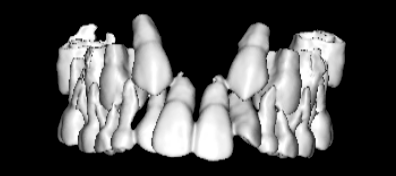

治療法:上顎急速拡大装置+クリアスナップ+フェイスマスク+上顎3番は開窓牽引CT写真にて位置確認

(難症例のため、小児期の矯正を2段階に設定しました)

検査時のレントゲン分析では、上下顎の関係は、上顎の劣成長があり下顎前突傾向という値がでておりましたが、前歯ジャンプ後はフェイスマスクの効果もあり、上下顎の関係は正常化しています。

上顎が若干優位になっていますので、今後の下顎の成長のための貯金になっているくらいです。